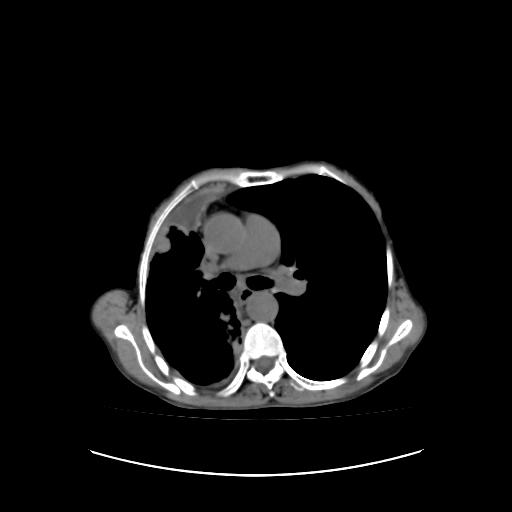

可见多发肺内病灶,且胸膜病灶较多有圆球状而非丘状,多考虑胸膜转移瘤伴胸腔积液,右侧胸廓缩小固定,且部分病灶呈丘状,尚不除外恶性胸膜间皮瘤伴肺内转移

右侧胸膜增厚,局部呈结节状增厚,右侧胸腔少量积液。双肺未见确切肿块影。纵隔未见淋巴结肿大。气管、支气管通畅。考虑右侧胸膜间皮瘤(恶性?)可能性大。不除外癌性胸膜炎。

右侧胸廓塌陷,右侧胸膜广泛增厚并见多发胸膜结节,右侧少量胸腔积液并包裹。

右侧广泛胸膜增厚,局部呈结节状增厚,右侧胸腔少量积液。双肺未见确切肿块影。纵隔未见淋巴结肿大。气管、支气管通畅。考虑右侧胸膜间皮瘤(恶性?)可能性大。支持!